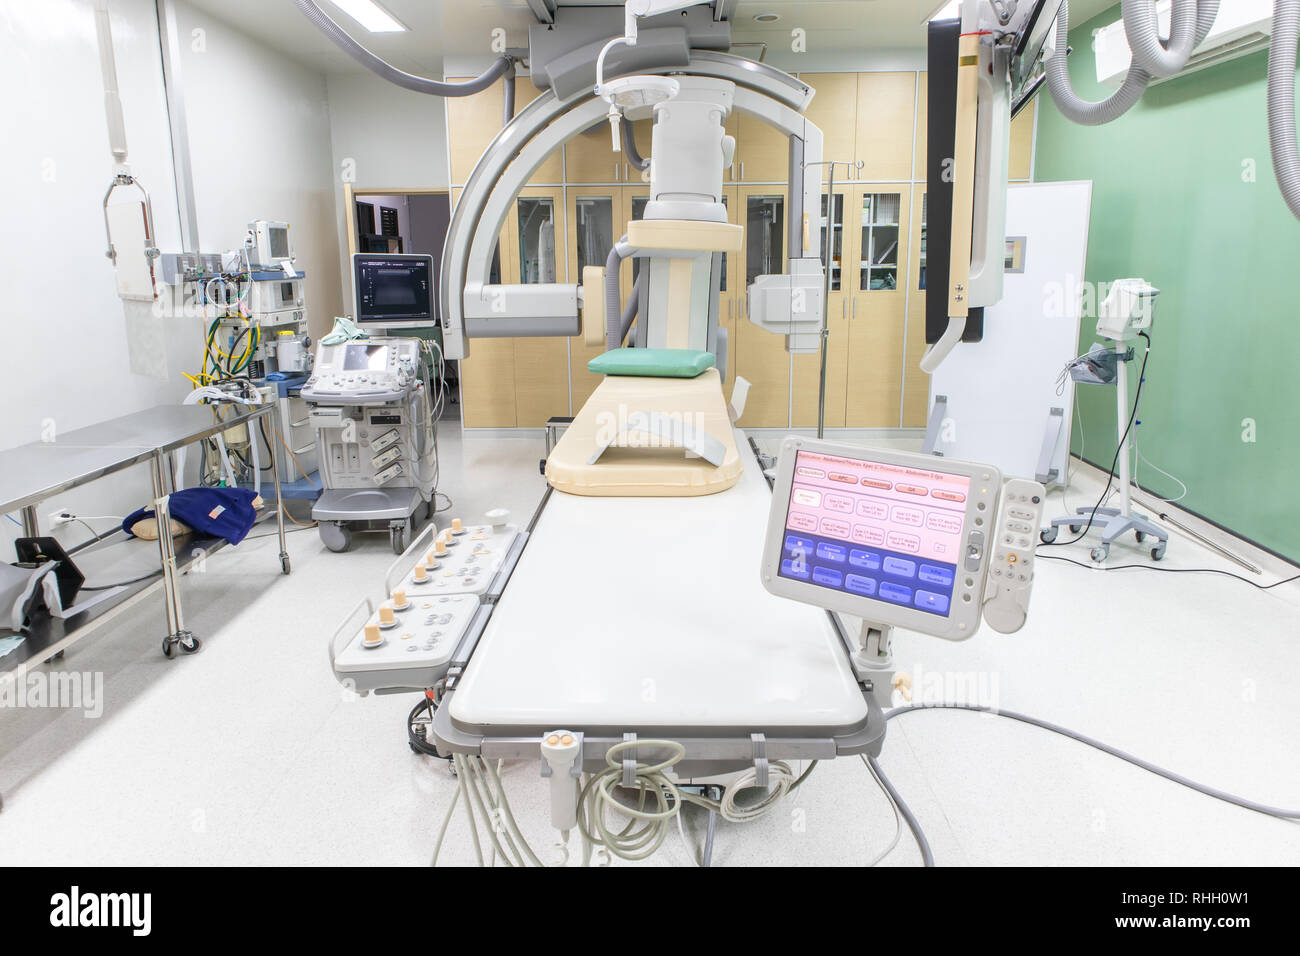

Digital Subtraction Angiography Room, DSA lab, operating room with X-ray medical scan in hospital. Stock Photohttps://www.alamy.com/image-license-details/?v=1https://www.alamy.com/digital-subtraction-angiography-room-dsa-lab-operating-room-with-x-ray-medical-scan-in-hospital-image234557821.html

Digital Subtraction Angiography Room, DSA lab, operating room with X-ray medical scan in hospital. Stock Photohttps://www.alamy.com/image-license-details/?v=1https://www.alamy.com/digital-subtraction-angiography-room-dsa-lab-operating-room-with-x-ray-medical-scan-in-hospital-image234557821.htmlRFRHH0W1–Digital Subtraction Angiography Room, DSA lab, operating room with X-ray medical scan in hospital.

Digital Subtraction Angiography Room, DSA lab, operating room with X-ray medical scan in hospital. Stock Photohttps://www.alamy.com/image-license-details/?v=1https://www.alamy.com/digital-subtraction-angiography-room-dsa-lab-operating-room-with-x-ray-medical-scan-in-hospital-image234557835.html

Digital Subtraction Angiography Room, DSA lab, operating room with X-ray medical scan in hospital. Stock Photohttps://www.alamy.com/image-license-details/?v=1https://www.alamy.com/digital-subtraction-angiography-room-dsa-lab-operating-room-with-x-ray-medical-scan-in-hospital-image234557835.htmlRFRHH0WF–Digital Subtraction Angiography Room, DSA lab, operating room with X-ray medical scan in hospital.

Digital Subtraction Angiography Room, DSA lab, operating room with X-ray medical scan in hospital. Stock Photohttps://www.alamy.com/image-license-details/?v=1https://www.alamy.com/digital-subtraction-angiography-room-dsa-lab-operating-room-with-x-ray-medical-scan-in-hospital-image234557793.html

Digital Subtraction Angiography Room, DSA lab, operating room with X-ray medical scan in hospital. Stock Photohttps://www.alamy.com/image-license-details/?v=1https://www.alamy.com/digital-subtraction-angiography-room-dsa-lab-operating-room-with-x-ray-medical-scan-in-hospital-image234557793.htmlRFRHH0T1–Digital Subtraction Angiography Room, DSA lab, operating room with X-ray medical scan in hospital.

Digital Subtraction Angiography Room, DSA lab, operating room with X-ray medical scan in hospital. Stock Photohttps://www.alamy.com/image-license-details/?v=1https://www.alamy.com/digital-subtraction-angiography-room-dsa-lab-operating-room-with-x-ray-medical-scan-in-hospital-image234557799.html

Digital Subtraction Angiography Room, DSA lab, operating room with X-ray medical scan in hospital. Stock Photohttps://www.alamy.com/image-license-details/?v=1https://www.alamy.com/digital-subtraction-angiography-room-dsa-lab-operating-room-with-x-ray-medical-scan-in-hospital-image234557799.htmlRFRHH0T7–Digital Subtraction Angiography Room, DSA lab, operating room with X-ray medical scan in hospital.

Digital Subtraction Angiography Room, DSA lab, operating room with X-ray medical scan in hospital. Stock Photohttps://www.alamy.com/image-license-details/?v=1https://www.alamy.com/digital-subtraction-angiography-room-dsa-lab-operating-room-with-x-ray-medical-scan-in-hospital-image234557830.html

Digital Subtraction Angiography Room, DSA lab, operating room with X-ray medical scan in hospital. Stock Photohttps://www.alamy.com/image-license-details/?v=1https://www.alamy.com/digital-subtraction-angiography-room-dsa-lab-operating-room-with-x-ray-medical-scan-in-hospital-image234557830.htmlRFRHH0WA–Digital Subtraction Angiography Room, DSA lab, operating room with X-ray medical scan in hospital.